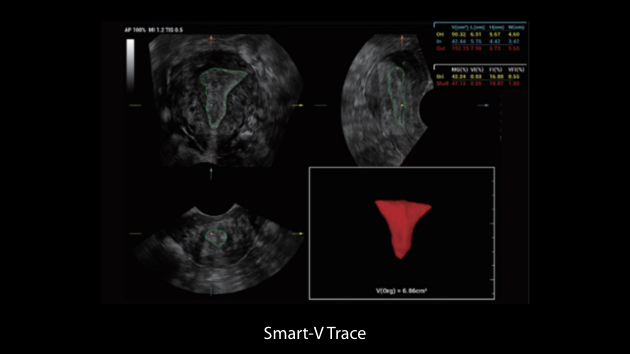

El sistema Nuewa I9, dise?ado exclusivamente para la atenciĂłn mĂ©dica neonatal y de mujeres, brinda una experiencia innovadora integral. Estas innovaciones se desarrollan sobre la base de un conocimiento profundo de situaciones clĂnicas complejas para proporcionar respuestas precisas y oportunas, una gran eficiencia y una experiencia de usuario extraordinaria.

La plataforma ZST+?es una innovaciĂłn extraordinaria que representa toda una evoluciĂłn en el ĂĄmbito de la ecografĂa. Transforma las mĂ©tricas ecogrĂĄficas de la formaciĂłn de haces convencional al procesamiento basado en datos de canal. Supera la limitaciĂłn tradicional de tener que equilibrar entre resoluciĂłn espacial, resoluciĂłn temporal y uniformidad del tejido, con lo que ofrece una calidad de imagen excepcional para soluciones de producciĂłn de imĂĄgenes infinitas con mejoras continuas.